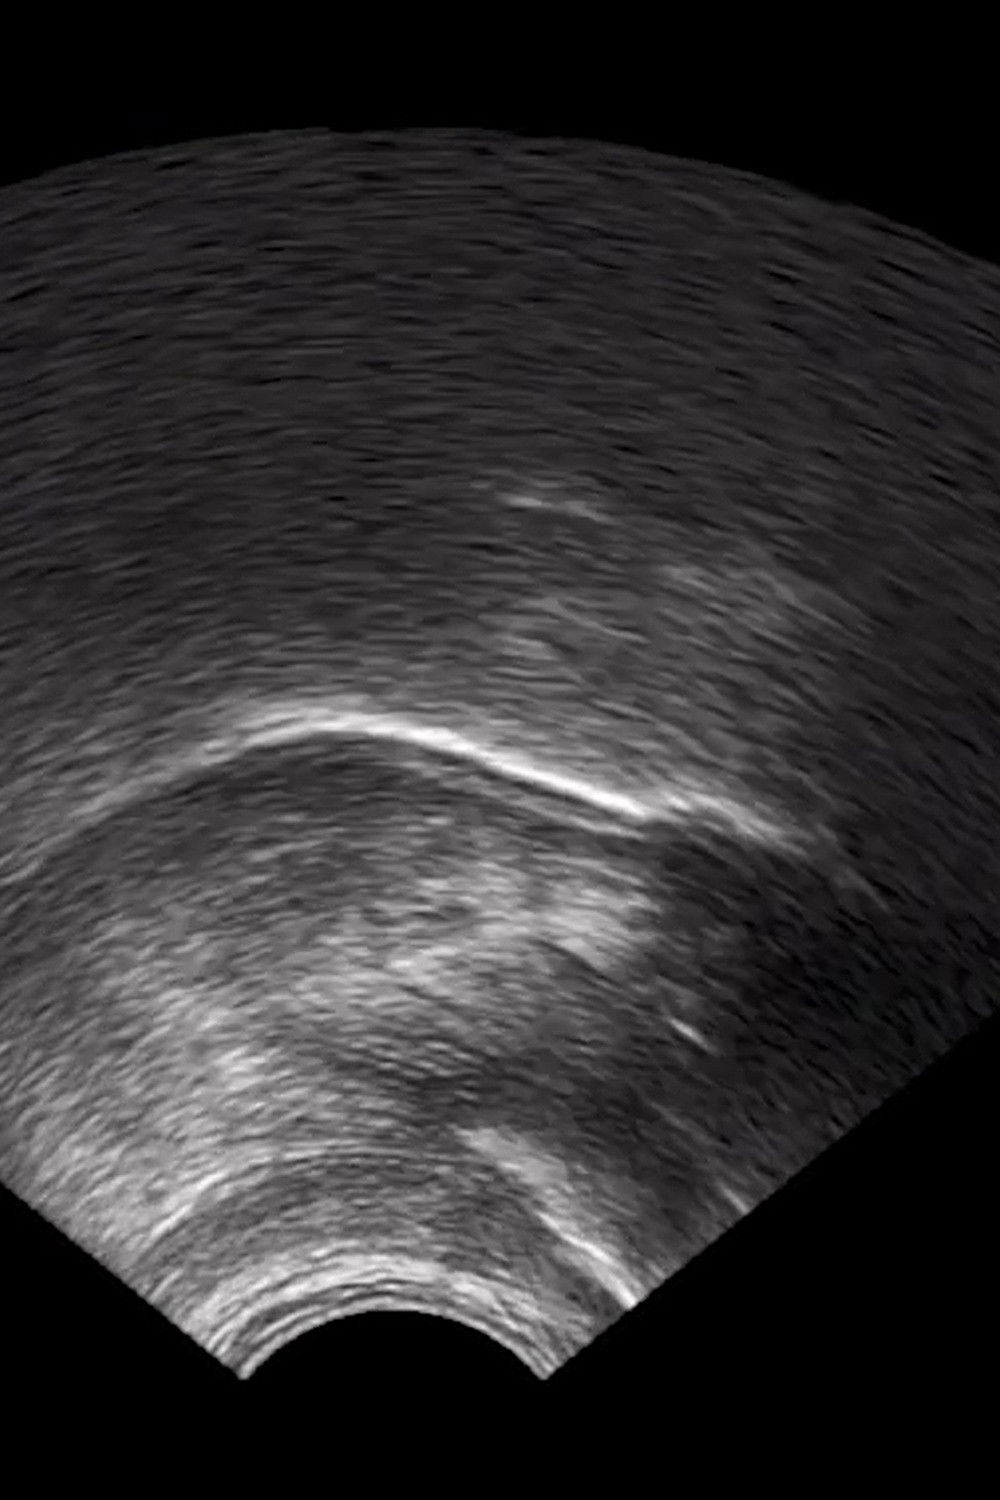

What are we looking at? We can perhaps discern from the greyscale fuzz, the varying degrees of white patches, fanning out from a point in shapes hard to parse, that this is an ultrasound display. But what are we trying to see in the scan? There is no baby or foetal development, no heart, no kidney, no liver, no needle to pierce through the night like a ship. But it moves in time with a voiceover. A mouth, surely? Yes. We are, quite literally, mechanically, watching someone speak.